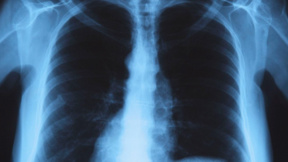

"Когато пуснеш силно душа, се създава един аерозол в помещението и ако вдишаш голямо количество от микробите, се развива тежка легионелна пневмония.

Отиваме ли в хотел или помещение, където не се е използвала банята или водопроводна вода, първо трябва да включим инсталацията за вентилация, да пуснем душа и чешмата и да излезем. След няколко минути, спирайки дишането, спираме водата, продължава да работи вентилационната система и по този начин намаляваме сто пъти вероятността, когато се изкъпем или ползваме чешмата, да се разболеем от легионела".